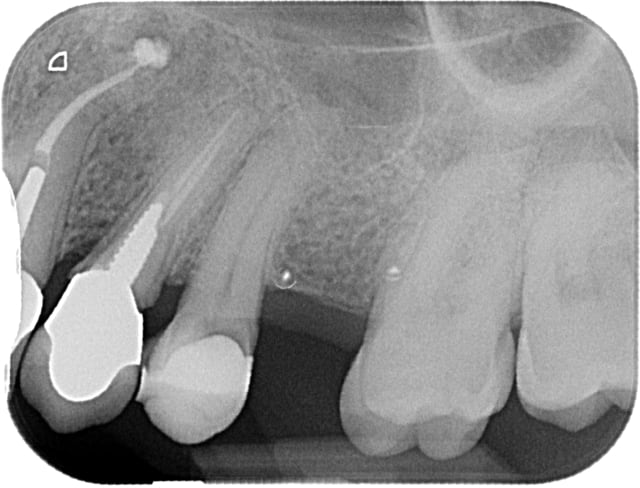

11 et 21 sont vitales.

pour le haut je ne suis pas sur que la forme de la 12 soit très esthétique,

ainsi est-ce que refaire la 12 et cc pour 22 21 11 parait pertinent ?

sauf que si on refait 12 en gardant l'inlay-core ( je suis toujours prudent avec les déposes !!), cela vaut-il le coup de faire des cc ?

22 21 et 11 ce sont des indications de facettes, pourquoi mutiler complètement la dent ?

Pour la 22 qui est intacte, pourquoi pas. Pour les deux autres, à partir du moment où on a un composite proximal qui va également sur la face palatine, j'estime que la couronne est mieux indiquée. Le jour où on aura une infiltration, on sera bien embêté. Pourquoi s'empêcher de soigner totalement quelqu'un sous des prétextes intellectuels.

OK on y voit plus clair, si on prend l'image comme une référence, ce qui me choc autant que le bloc antérieur d'un point de vue esthétique (et là encore c'est une vision subjective donc à faire valider au patient d'abord), c'est la position de 14, 15 ,16, ingressées suite à affaissement occlusal, oui je sais c'est fonctionnel, mais c'est moche aussi!!!!